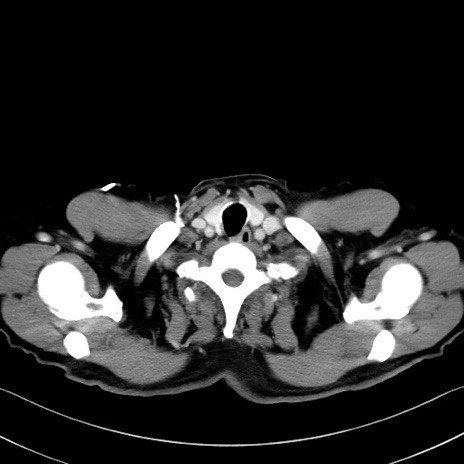

冠状断像